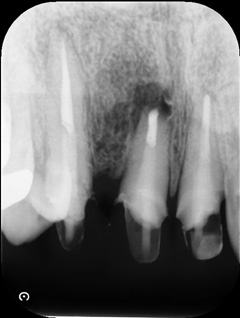

根もとにフィステル(黒)ができています。切開やレーザーを照射しても再発します。

矯正をした歯なので、根の先が吸収しています。

CT検査をしました。再根管治療をおこなっても、根が吸収してるので、歯が薄くなり、抜歯に近くなります。

術後のレントゲンです。